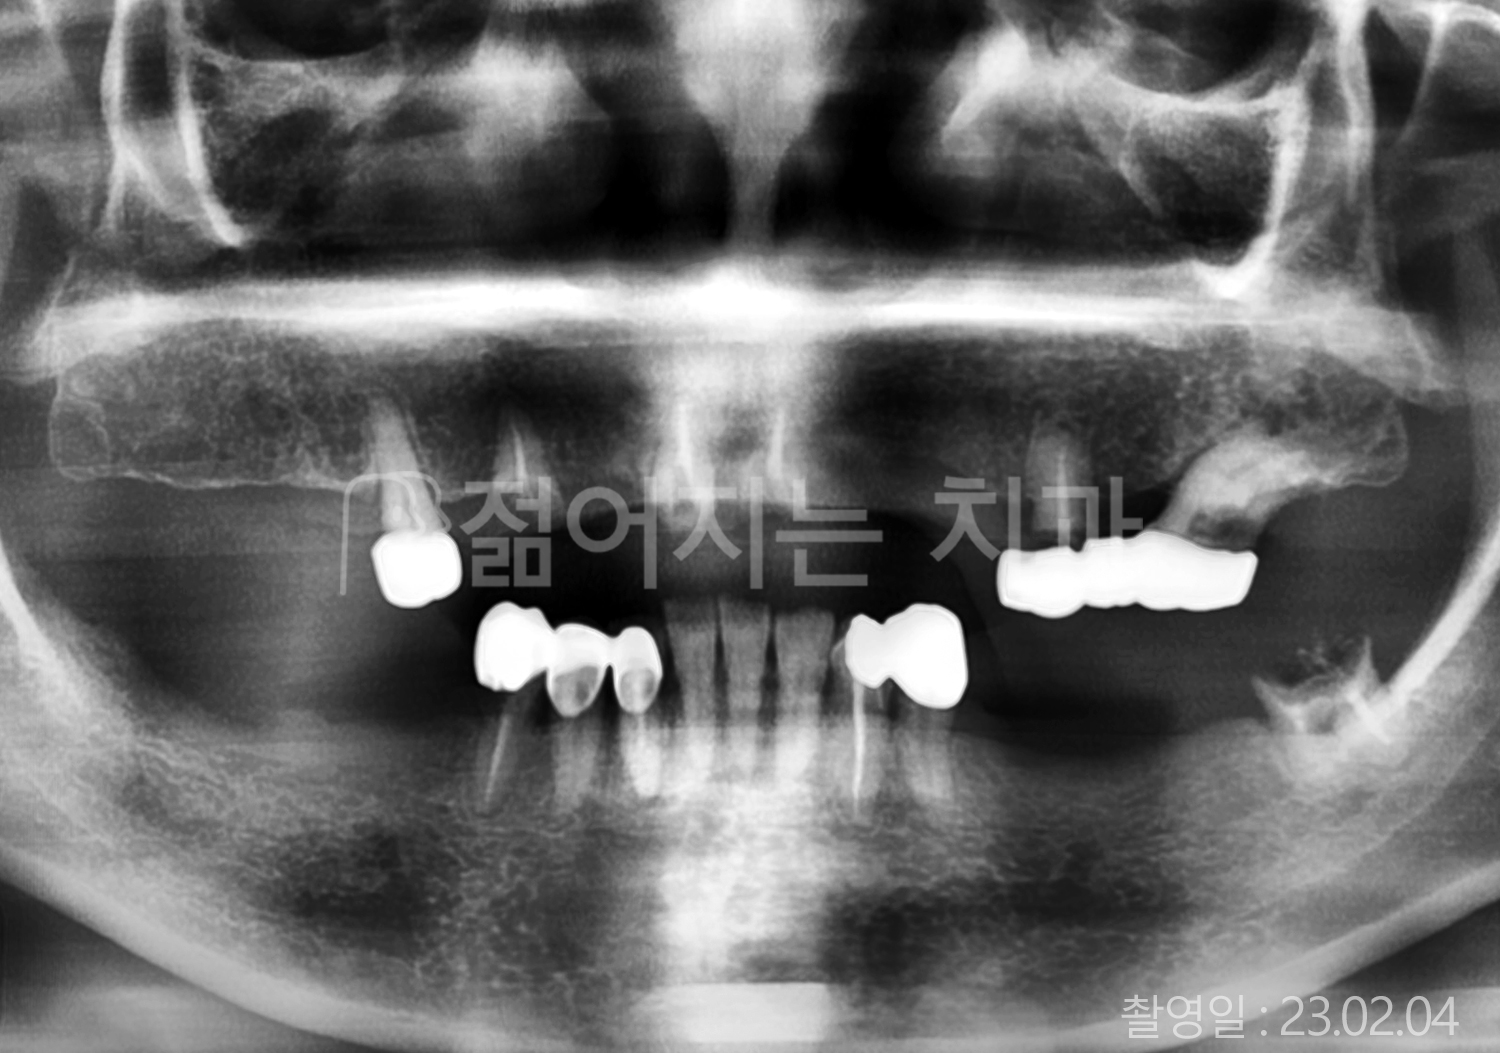

• 80대 전체치아 10개 이상 임플란트

• 60대 고혈압, 당뇨, 고지혈증 전체치아 10개 이상 임플란트

• 60대 전체치아 10개 이상 임플란트

• 60대 고혈압, 고지혈증 전체치아 10개 이상 임플란트

• 50대 고혈압, 당뇨, 고지혈증 전체치아 10개 이상 임플란트

• 70대 골다골증, 파킨스병 전체치아 10개 이상 임플란트

• 40대 전체치아 10개 이상 임플란트

• 60대 골다골증 전체치아 10개 이상 임플란트

• 40대 고혈압 전체치아 10개 이상 임플란트

• 50대 전체치아 10개 이상 임플란트

• 70대 전체치아 10개 이상 임플란트